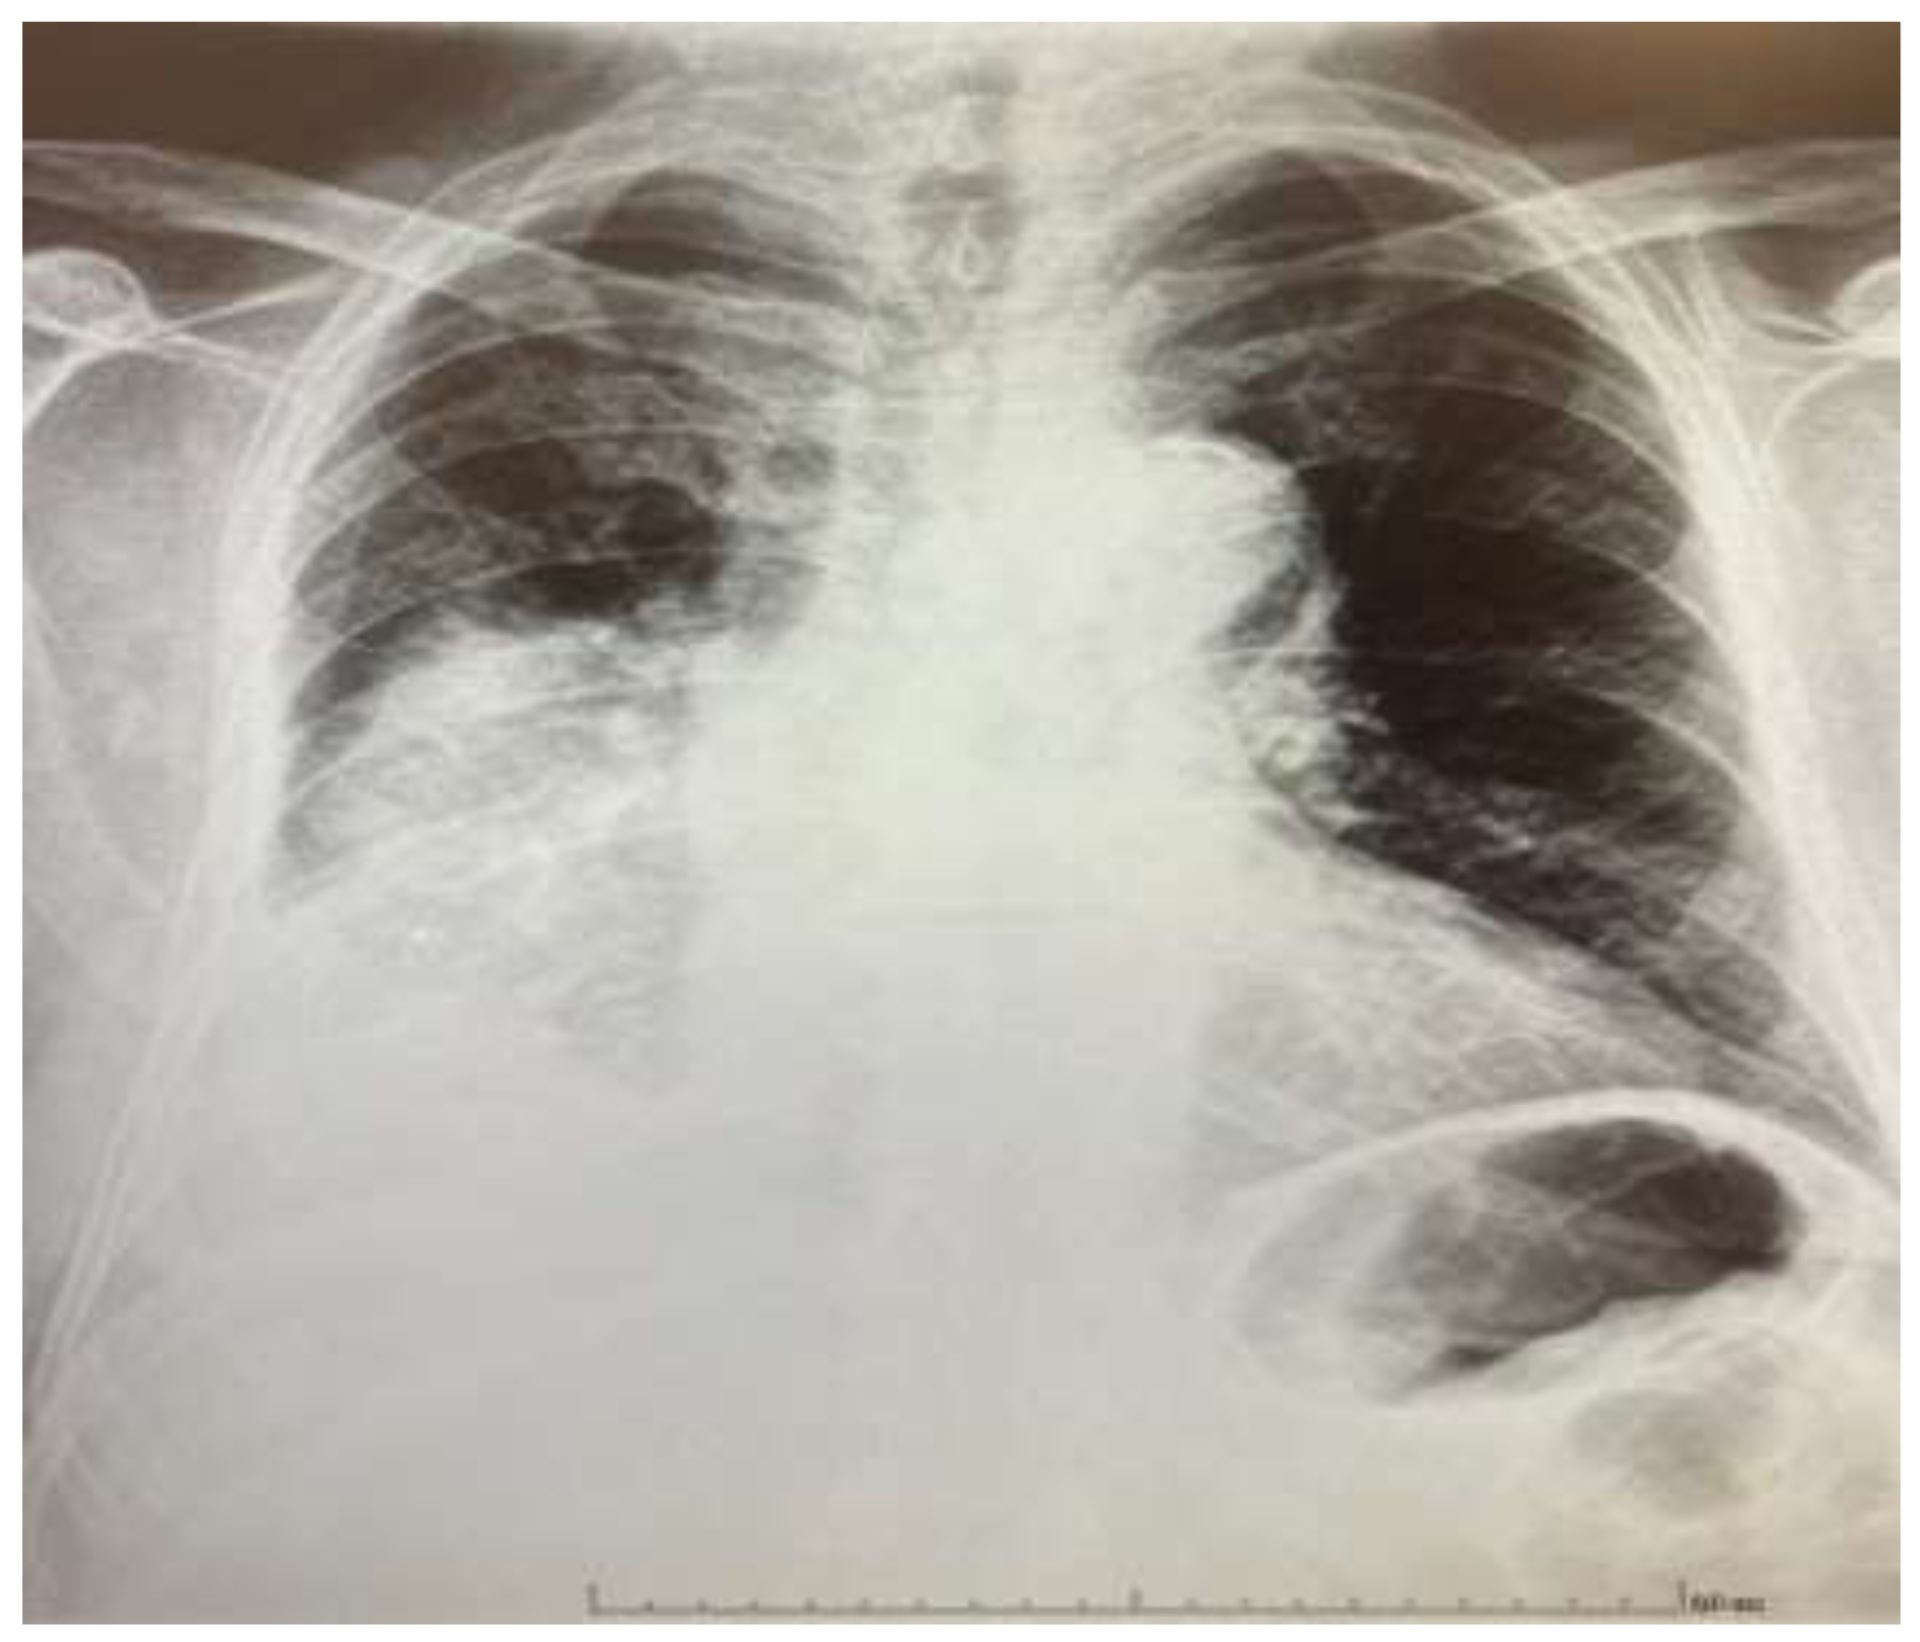

Ambulatory chest radiography (Figure 1), revealed findings consistent with pneumonia. Concurrently, laboratory analysis demonstrated a profound elevation in inflammatory markers, with a C-reactive protein (CRP) level of 595 mg/L (<5 mg/L). Given the severity of these findings, the patient was immediately referred for hospitalization.

Figure 1. Chest X-ray shortly before the patient was admitted to the hospital. Anteroposterior chest radiograph showing a dense opacity in the right lower and mid-zones, consistent with a right lower lobe consolidation and probably a small pleural effusion. The right upper zone remains partially aerated.